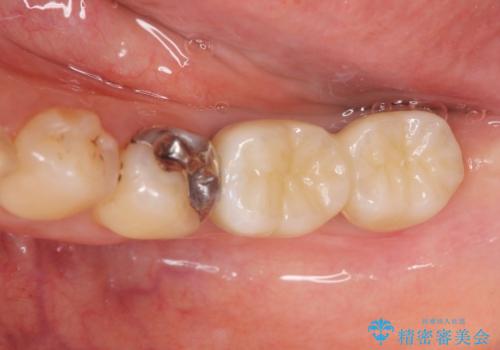

歯周病に対する全体治療

治療期間はかかりましたが、しっかりと歯周病治療・インプラント治療を行ったおかげで歯周病の状態は非常に良くなり、安定した咬合関係を確立することができました。

再生治療、歯周外科を行うことで歯周病治療を行い、残すことのできる歯の歯周環境を整える。

残すことのできない歯は抜去したのち骨造成を含めたインプラント治療を行い、しっかりとした咬合関係を確立していきます。